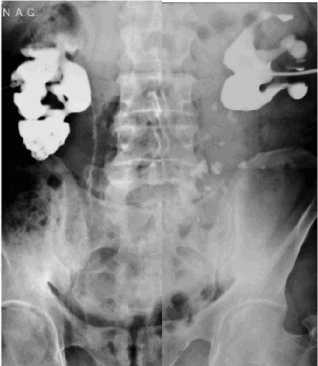

• Пиелография (внутривенная, ретроградная/антеградная):

о Узловые пристеночные рентгеннегативные дефекты наполнения небольшого размера в просвете мочеточника

о Вдавление краев мочеточника (вид в профиль)

о Стенка мочеточника может иметь шероховатый вид, вследствие слияния групп небольших кист

(Слева) Внутривенная пиелография в экскреторную фазу, прямая проекция: несколько пристеночных дефектов наполнения небольших размеров в левом мочеточнике, в проксимальном его отделе и в середине. Эти признаки характерны для кистозного уретерита.

При антеградной пиелоуретерографии отмечается нарушение пассажа контраста по мочеточникам с наличием множественных сферических внутрипросветных дефектов наполнения (рис. 2).

Рисунок 2. Антеградная пиелоуретерография

Figure 2. Antegrade pyeloureterography